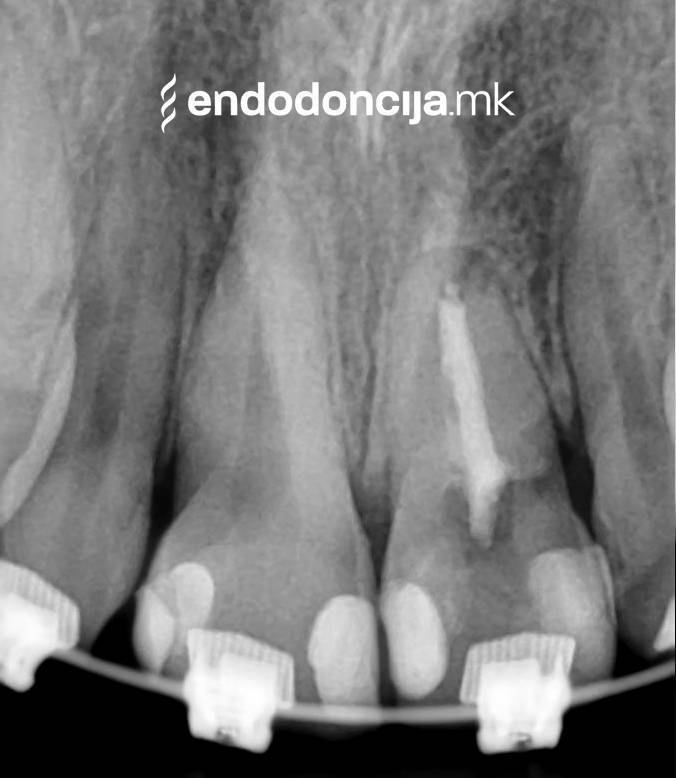

Εκτός από την ανίχνευση των ριζικών καναλιών, η ενδελεχής προετοιμασία και η απολύμανση του ριζικού σωλήνα είναι η προϋπόθεση για μια επιτυχημένη συνολική θεραπεία. Μέσω της χρήσης των νεότερων οργάνων και αντιβακτηριακών διαλυμάτων, όλα τα υπολείμματα ιστών και τα βακτήρια που υπάρχουν μπορούν να εξαλειφθούν.

Με τη σωστή θεραπεία, όχι μόνο οι οξείες φλεγμονές αλλά και οι χρόνιες μπορούν επίσης να αντιμετωπιστούν με επιτυχία. Αυτά μπορεί να προκαλέσουν πόνο ή μερικές φορές ακόμη και εντελώς χωρίς συμπτώματα. Η έγκαιρη ανίχνευση και εξάλειψη τέτοιων φλεγμονών είναι ζωτικής σημασίας για τη μακροχρόνια συντήρηση των δοντιών.